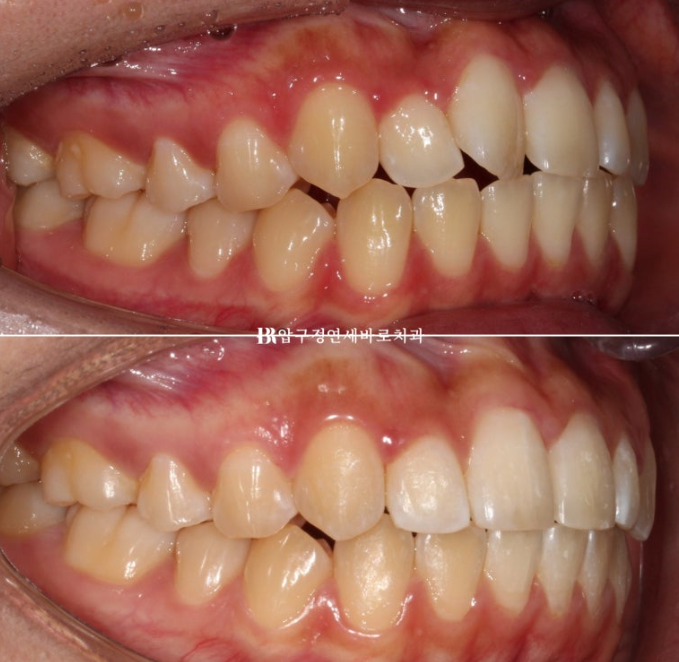

앞니 부분교정은 배열 이외에 별다른 기능이 없는 대신 작고 심플한 MTA 미니튜브나 설측 2D 교정장치를 사용합니다.

하지만 이 환자분은 덧니 이외에도 앞니 물리는 것이 얕은 절단교합을 보였기 때문에 앞니 배열 후 고무줄을 걸어 절단교합도 어느정도 해결하기로 했습니다.

따라서 고무줄 거는 기능이 있는 장치 클리피씨를 부착하고 교정을 진행했습니다.

24.05

치료시작 5개월째의 모습입니다.

앞니 부분교정은 앞니 6개에만 장치를 붙여서 진행합니다.

덧니는 거의 해결이 되었고 고무줄을 걸어서 앞니 교합이 깊어지도록 도모했습니다.

심한 덧니를 가지런하게 하기 위해 치간삭제도 소량 했습니다.

그리고 한달 후 24년 6월 드디어 치료를 마무리 했습니다.

24.06

배열은 가지런해졌고 앞니 교합도 처음에 비하여 깊어졌습니다.

전 후 비교 보겠습니다.

토탈 치료 기간은 6개월 입니다.

23.12~24.06